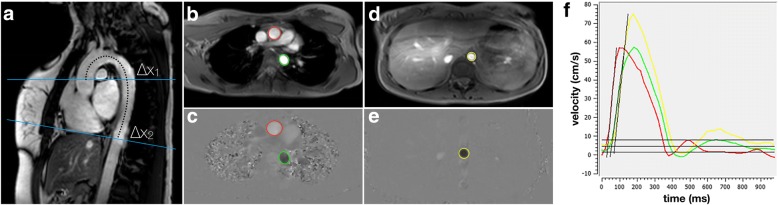

Subsequently, PWV was computed as x/t (m/s) with x being the aortic length between the ascending, proximal descending and distal descending thoracic aorta as measured along the centre lumen line and t being the time duration between the arrival of the systolic pulse wave at these locations. PWV was quantified utilizing validated, semi-automated tailored software program for measurement of PWV (MASS version 5.1, LKEB, Leiden, The Netherlands) and conforming to a standardized, validated procedure that has an excellent inter- scan, inter-rater and intra-rater reproducibility (ICC: 0.87–0.92) [8, 9, 11]. An experienced researcher (AE, 3 years experience in PWV assessment) measured the distance between the flow measurement planes in the ascending to proximal descending, proximal descending to distal descending and total thoracic aorta within the double oblique image by manually tracing the aorta along its centreline between each measurement site. Subsequently, using a semi-automatic flow analysis tool in MASS, the outer contours of the ascending and proximal descending (VE acquisition 1) as well as the distal descending (VE acquisition 2) thoracic aorta were traced in all 50 images of the two VE acquisitions to generate two aortic velocity maps. From these aortic velocity maps, a second customized software program (PwvAppStatic, LKEB, Leiden, The Netherlands) generated velocity-time graphs that were used to calculate the time delay between the arrival of the systolic pulse wave at the three measurement sites. By combining the time delay and aortic lengths, the software PwvAppStatic computed the absolute PWV value (m/s) in each of the three measurement sites via linear regression modelling. Figure 2 provides an example of the double oblique and through-plane VE images of the thoracic aorta as well as an illustration of PWV quantification.

Fig. 2.

Examples of double-oblique and through-plane velocity-encoded images of the thoracic aorta and of pulse wave velocity (PWV) quantification. Sagittal double oblique acquisition (panel a) serves as the input for planning velocity-encoded acquisitions at the level of the ascending (top blue line in a and red contours in b and c) and descending aorta (green contours in b and c). A more distant cross section at the level of the diaphragm is also acquired (bottom blue line in a, and yellow contours in d and e). PWV = Δx/Δt, where Δx is the distance between the ascending aorta and the proximal descending aorta (Δx1) or the aorta at the level of the diaphragm (Δx2), and Δt is the time difference between the two velocity-time curves as plotted in (f)”